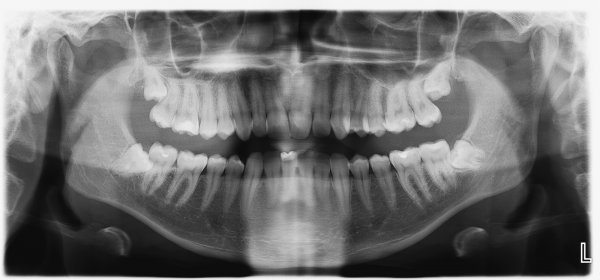

Зубы мудрости — самые заметные рудименты человека. За годы эволюции наша пища стала менее жесткой, и «восьмерки» стали не особо нужны. К тому же наш мозг увеличился в размерах, челюсти — уменьшились, поэтому прорезаться из десен зубам мудрости стало трудно.

Сейчас у большинства людей зубы мудрости вылезают медленно. Пока это происходит, во рту может развиться инфекция, иногда зубам не хватает места и они вырастают под наклоном. Поэтому от «восьмерок» избавляются не только хирурги, но и эволюция.

У людей появилась мутация, из-за которой один или несколько зубов мудрости вообще не появляются — нет даже их зачатков. За несколько тысяч лет эта особенность распространилась весьма широко: сейчас, по разным данным, зубов мудрости недосчитываются от 5 до 40% всех жителей Земли.